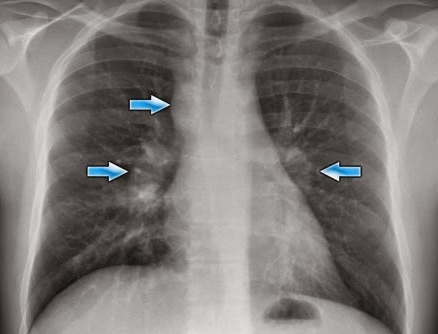

【肺門陰影増強の写真】

次の写真は両側の肺門陰影の増大が認められる。一般的に肺門陰影増大の原因としてはリンパ腺腫や静脈の拡張である。この写真では右の気管部の腫瘤が非常に特徴的で診断に有用。左右の肺門陰影の増強と右の気管支、および傍気管部の陰影。これはサルコイドーシスに見られる所見であり、”1-2-3サイン”とも呼ばれている。

Chest Medicine Made Easy-Dr Deepu: BASICS OF CHEST X RAY-PART 5, THE HILUM AND MEDIASTINUM